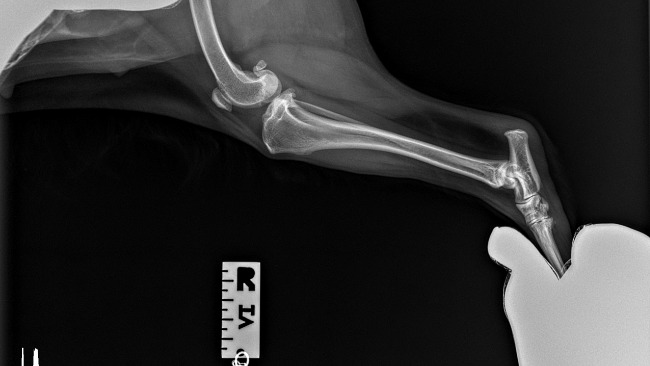

Jestem Melania, psiakiem, który ma 4 lata i 3 miesiące, od pewnego czasu mam problem z chodzeniem, teraz nie jestem w stanie wchodzić po schodach, spacerować, biegać za piłeczka ani normalnie funkcjonować. Leżę cały czas, śpię i staram się nie wychodzić. Moja Pani mówi ze wszystko będzie dobrze, ze będę jeszcze kiedyś szczęśliwym, pełnym energii pieskiem. Teraz potrzebujemy wsparcia finansowego, ponieważ leczenie i dotychczasowe badania sporo nas kosztowały. Zbieraliśmy pieniądze na rezonans, który po konsultacji z doktorem w klinice Auxilium okazał się niepotrzebnym i dodatkowym dla mnie stresem. Dziś miałyśmy termin tego badania DIAGNOZA NIESTETY BYŁA NAJGORSZA - będzie potrzebna OPERACJA STAWÓW (ZERWANIE WIĘZADŁA KRZYŻOWEGO). Został wykonany mi test kompresyjny, który okazał się obustronnie dodatni oraz u mnie wystąpiła reakcja bólowa podczas jego wykonywania. Dodatkowo wykonano mi dwa zdjęcia RTG samych stawów (załączamy je). Obustronnie prawidłowe reakcje korektury kończyn piersiowych i miedniczych, prawidłowe odruchy kolanowe, piszczelowe i cofania kończyn. Zwróciliśmy się z zapytaniem do administratora portalu pomagam.pl czy dotychczasowe pieniążki uzbierane na rezonans możemy przepisać na zbiórkę operacji i oczywiście wyrazili zgodę. Po prostu przekształcamy tę zbiórkę. Chcemy teraz Was - ludzi o wielkim, ciepłym serduszku poinformować o stanie Melanii. Wcześniej pisaliśmy, że może być tak, "że przejdę poważną operację, po której dopiero dojdę do siebie, ale moja Pani powiedziała, że nigdy się nie poddamy i zrobimy wszystko, żebym była zdrowa. Jestem jeszcze młodziutka i całe życie przede mną dlatego będę bardzo wdzięczna za każdą formę pomocy". Dziś jesteśmy pewne, że operacja odbyć się musi, stawy które mogą zostać mi wstawione kosztują 2500 zł za jeden, co w moim przypadku trzeba pomnożyć przed dwa. Wybór tej metody, czyli pozwoli mi na swobodne poruszanie i wykonywanie podstawowych funkcji życiowych. Droga do diagnozy była dla nas naprawdę długa i kosztowna. Jest wyczerpana, teraz marzę o tym, żeby moje tylne łapki już dłużej nie sprawiały mi tyle bólu :( .Pani mówi, że pozostaje nam czekać, czy uda nam się uzbierać pieniążki na moją operację? Doktor powiedział, że dwa tygodnie się czeka od zarezerwowania terminu ;(